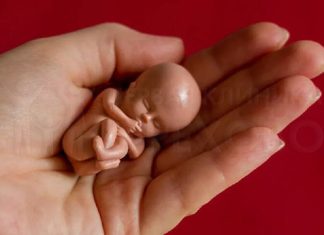

Неразвивающаяся беременность представляет собой патологию, характеризующуюся гибелью плода, аномалиями в инертности миометрия и сбоями во внутреннем балансе организма.

По-другому эта патология называется замершей беременностью. Данное...